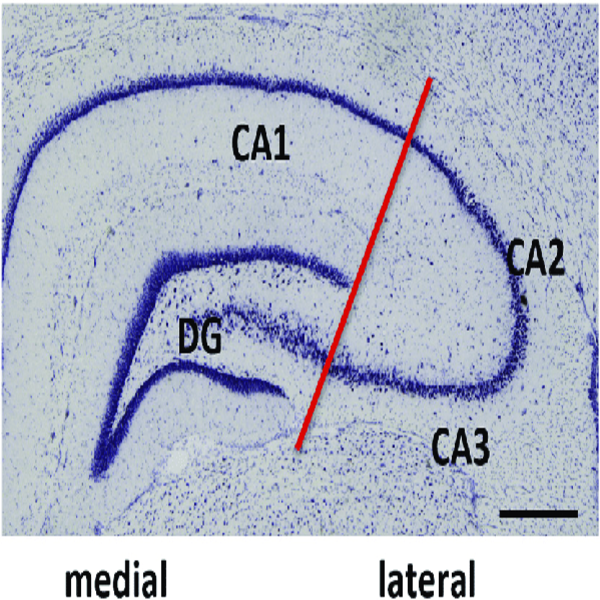

- General and specialized tissue and cell staining

- Prepare educational slides for students from all available tissues

Histological methods includes sample processing in the pathology laboratory, preparation of the slide and its examination under a microscope, sample fixation, molding, microtome cutting, staining and assembly of the slides.